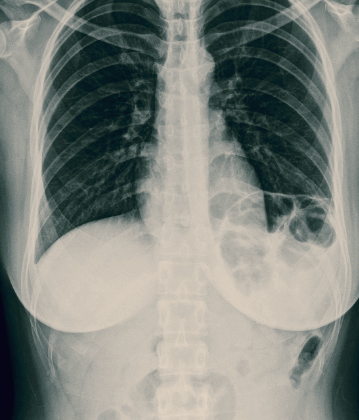

탈장이란 신체의 장기가 제자리에 있지 않고 다른 조직을 통해 돌출되거나 빠져나오는 증상을 말합니다. 신체 어느 곳에나 생길 수 있지만 대부분의 탈장은 복벽, 즉 배 안의 앞쪽의 벽에서 발생하는데, 복벽 탈장은 복강을 둘러싼 근육과 근막 사이에 복막이 주머니 모양으로 돌출되어 비정상적인 형태를 이루는 상태입니다. 주머니 속에 복강 내 장기가 포함되기도 한다. 탈장은 생긴 부위에 따라 여러 가지로 분류되기도 합니다.